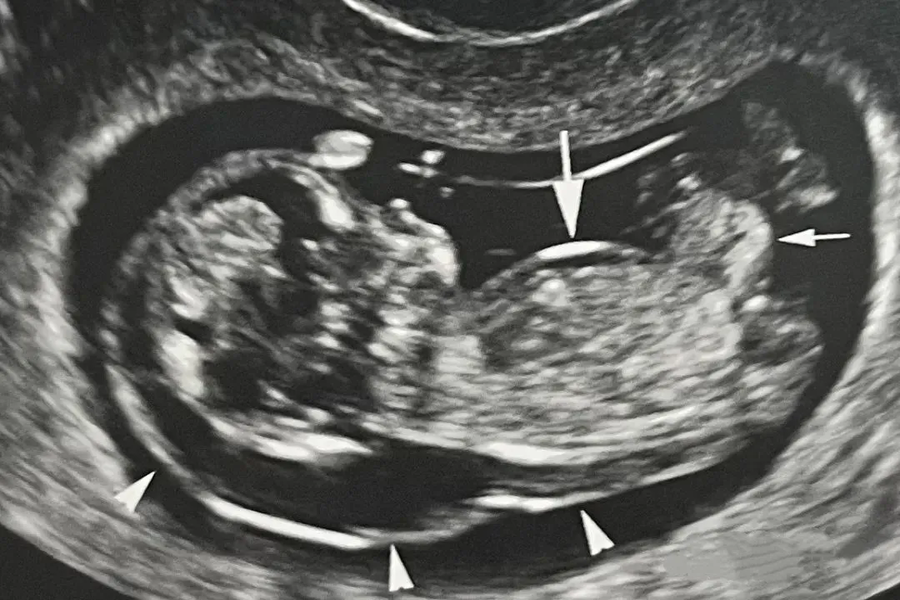

Hội chứng này có thể được sàng lọc sớm ngay trong 3 tháng đầu thai kỳ thông qua các phương pháp như xét nghiệm sàng lọc không xâm lấn qua máu mẹ, siêu âm hình thái đo độ mờ da gáy. Các trường hợp sàng lọc thai nguy cơ cao sẽ được tư vấn chẩn đoán trước sinh bằng các phương pháp sinh thiết gai nhau, chọc hút dịch ối.

Hội chứng Down được sàng lọc thông qua siêu âm hình thái, đo độ mờ da gáy ở tuần thai 11 đến 13 tuần 6 ngày

ThS. BSNT Nguyễn Đức Anh - Chuyên gia Di truyền, Trung tâm Y học Bào thai, Bệnh viện Đại học Phenikaa cho biết: "Đa số các dị tật bẩm sinh, đặc biệt là các bất thường lớn về hình thái và nhiễm sắc thể, có thể được phát hiện thông qua siêu âm đo độ mờ da gáy ở tuần 11-13 và siêu âm hình thái học 4D ở tuần 18-22. Kết hợp với các xét nghiệm như NIPT hay chẩn đoán xâm lấn nếu có chỉ định, chúng ta có thể đánh giá toàn diện các vấn đề mà thai nhi có thể gặp."